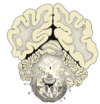

Label the diagram

Label the diagram (MAJOR STRUCTURES ONLY!)